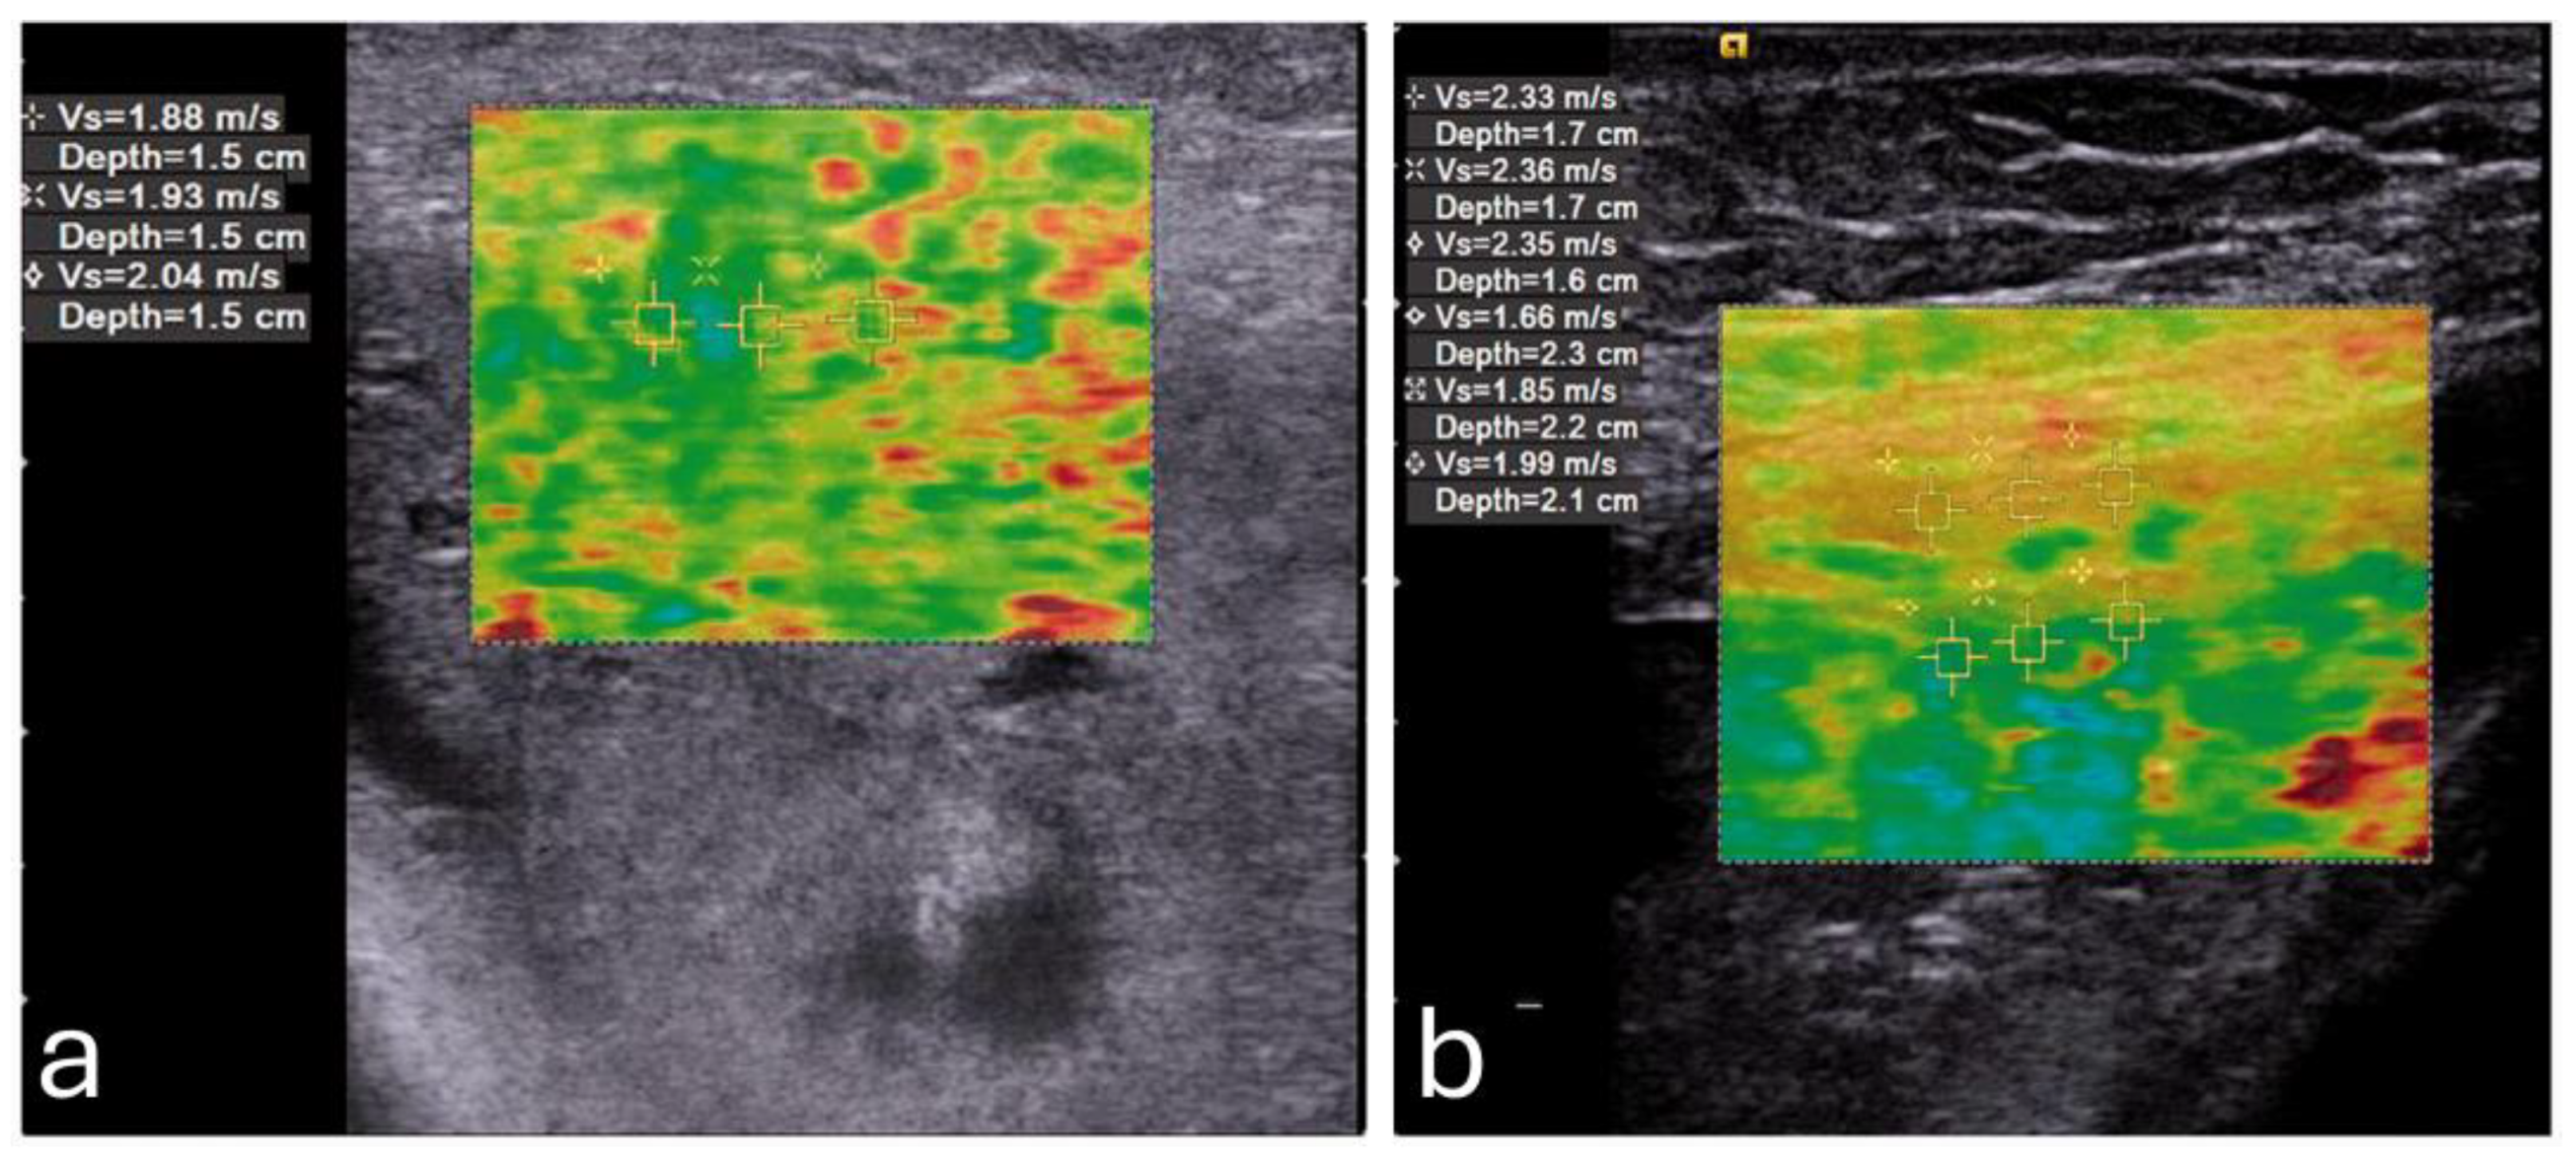

The assessment of fetal tissue elasticity using sonoelastography may provide a unique window into fetal development, offering both quantitative insights into tissue properties and valuable clinical markers for identifying developmental progress and potential complications. By measuring the elastic properties of key organs such as the lungs, liver, and brain, clinicians could potentially evaluate organ maturity, detect potential anomalies, and make informed decisions regarding perinatal care [58,59,60,61,62,63,64,65,66]. Figure 4 shows an example of normal lung and liver in a fetus.

Figure 4. Normal shear wave elastography images of fetal lung (a) and liver (b) with elasticity values of 4.43 kPa and 5.09 kPa respectively. Image adapted from Liu et al. [64] under a Creative Commons Attribution 4.0 International License. Changes were made to resize and adjust the images.